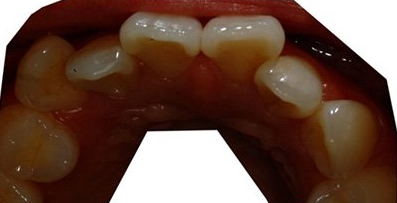

是治疗前的上牙照片。

很不整齐的样子。。。